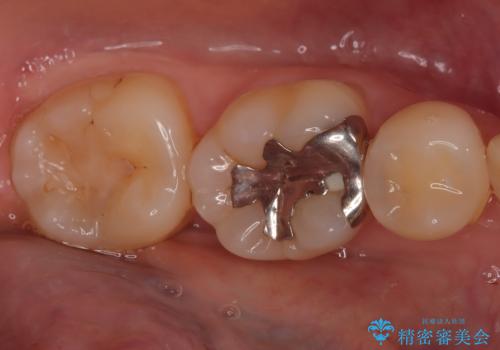

- 「銀歯を白くしたい」を主訴に来院された患者さんです。 左下6番に銀歯を被せてあり、一部分が欠けている状態でした。

銀歯と虫歯を除去しハイブリッドインレーで治療を行いました。